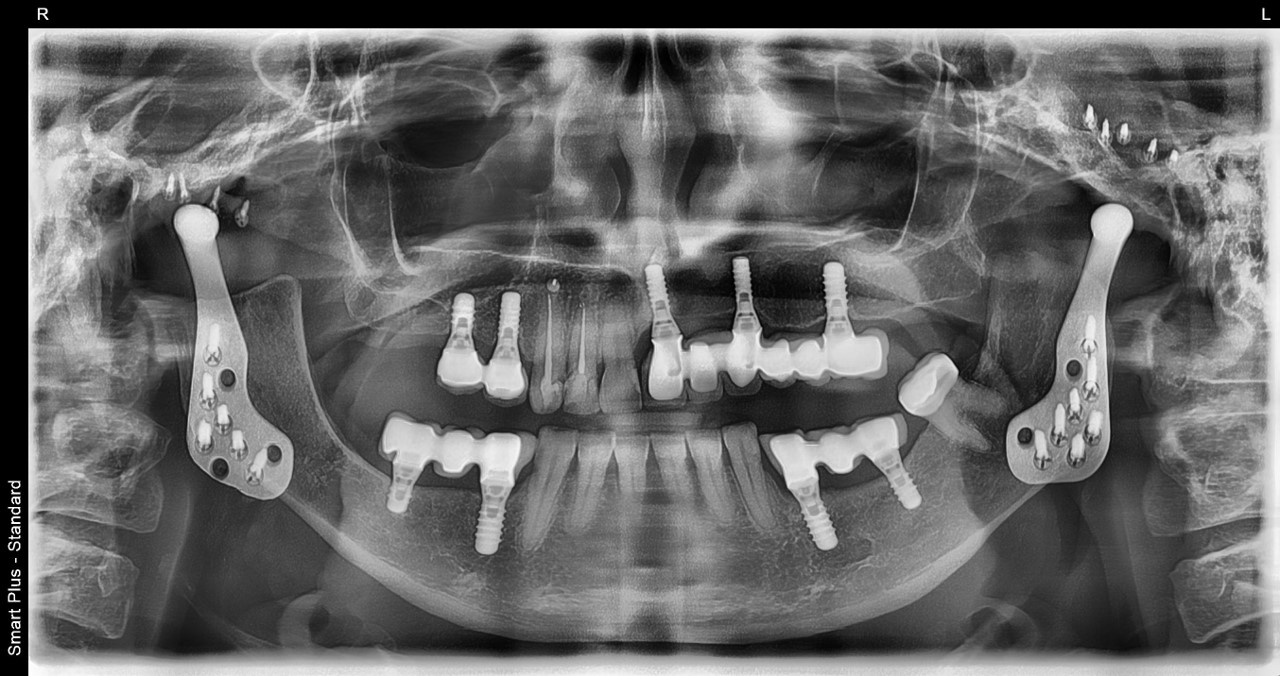

Σε περιπτώσεις προχωρημένης εκφυλιστικής νόσου της κροταφογναθικής ή αγκύλωσης μπορεί να γίνει δισκεκτομή και κονδυλεκτομή και άμεση αντικατάσταση του συνόλου της άρθρωσης από τεχνητή πρόσθεση, όπως γίνεται στις ολικές αρθροπλαστικές ισχύων ή γόνατος